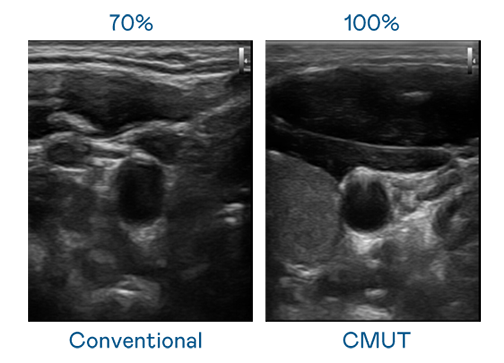

CMUT 技术是一种用电容式微机电元件来产生超音波讯号的技术。与传统 PZT 压电式技术相比,CMUT 频宽增加 30%,更宽频的超音波讯号让影像解析度大幅提升,是实现高影像品质医疗超音波扫描、促进精准医疗发展的关键技术。

超音波影像的解析度高低,首先取决于探头能发出的讯号频宽。asiagame CMUT 可提供高清晰的超音波讯号,提供高频宽、高灵敏度、影像纹理细节更高的超音波影像,协助医护人员缩短影像判读时间及利用精准的医疗影像进行诊断。